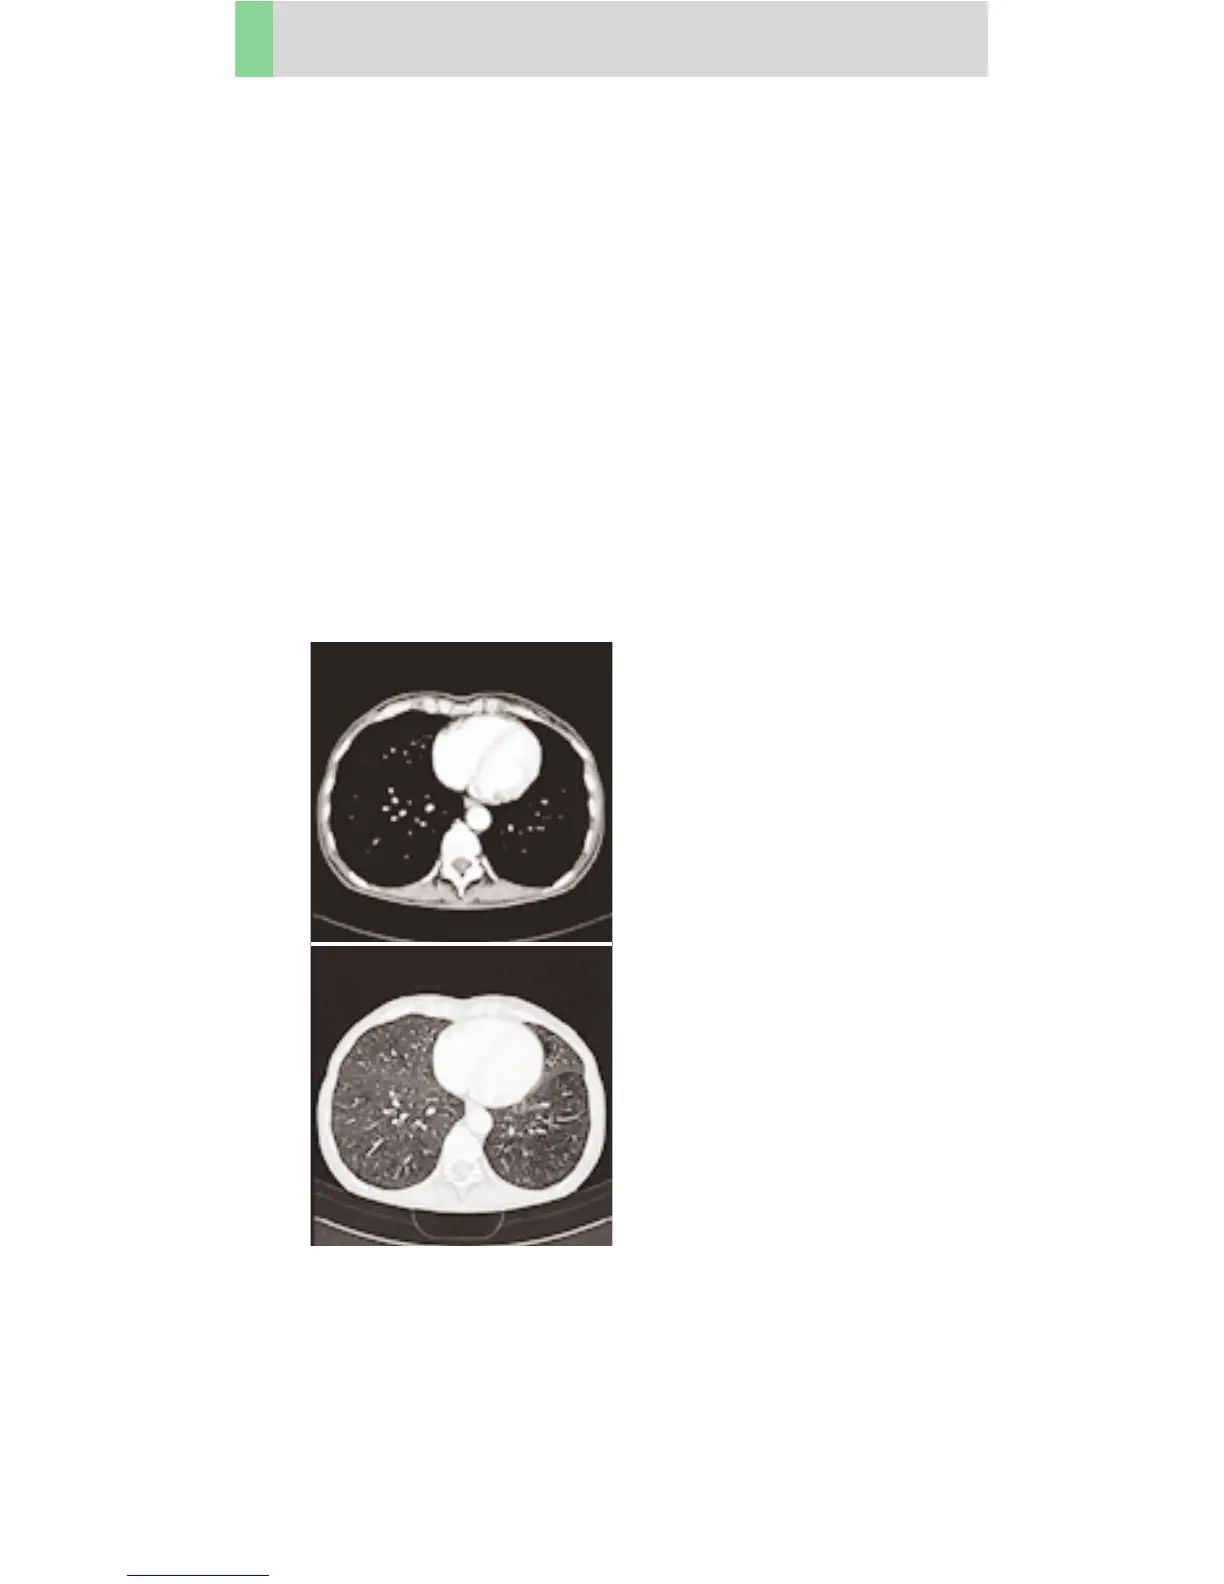

Thorax

ThoraxCombi06s

Indications:

Combining thin slice lung and routine thorax studies

with one spiral scan. E. g. thorax studies in general

and interstitial changes in the lungs, using a 0.6 sec.

rotation time.

There are two recon jobs predefined. The first one,

with 5 mm slice thickness, for the mediastinum,

the second reconstruction, with 1 mm slice thickness,

for the lung.

A range of 30 cm will be covered in 21.2 sec.